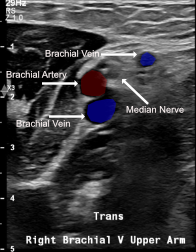

View brachial vein anatomy

Labeled ultrasound of right brachial vein upper arm showing brachial artery, paired brachial veins, and brachial nerve

• Brachial veins — Second choice: Paired veins adjacent to brachial artery (medial to lateral: brachial artery + median nerve); depth requires US guidance; risk of arterial puncture; use color Doppler to differentiate

• Brachial neurovascular bundle: brachial artery + paired brachial veins + median nerve — confirm vessel identity with color Doppler before access